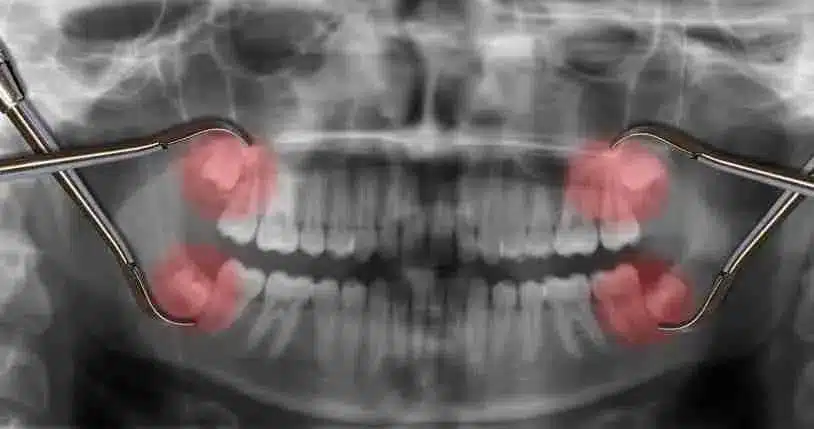

Another major point of confusion is wisdom tooth surgery. Many young adults in Singapore put this off because they heard that the wisdom tooth removal cost Singapore clinics charge is insanely high. They wait until the pain is unbearable, often during a busy work week in the CBD or right before a holiday at Marina Bay. By waiting for an emergency, you lose the ability to choose an affordable dentist Singapore 2026 option and often end up paying premium rates for a specialist on short notice.

Actually, the cost isn’t just about the surgery itself; it is about the complexity. If you do it early when the roots are not fully formed, it is much easier and cheaper. Furthermore, many people forget that as a CHAS Dentist Singapore, a clinic can help you offset a huge portion of the cost through government subsidies. If you have a CHAS card or belong to the Pioneer or Merdeka generation, the out-of-pocket “wisdom teeth surgery prices” becomes much more manageable. The best dental clinic Ang Mo Kio will always explain these financial options to you clearly before starting any procedure.